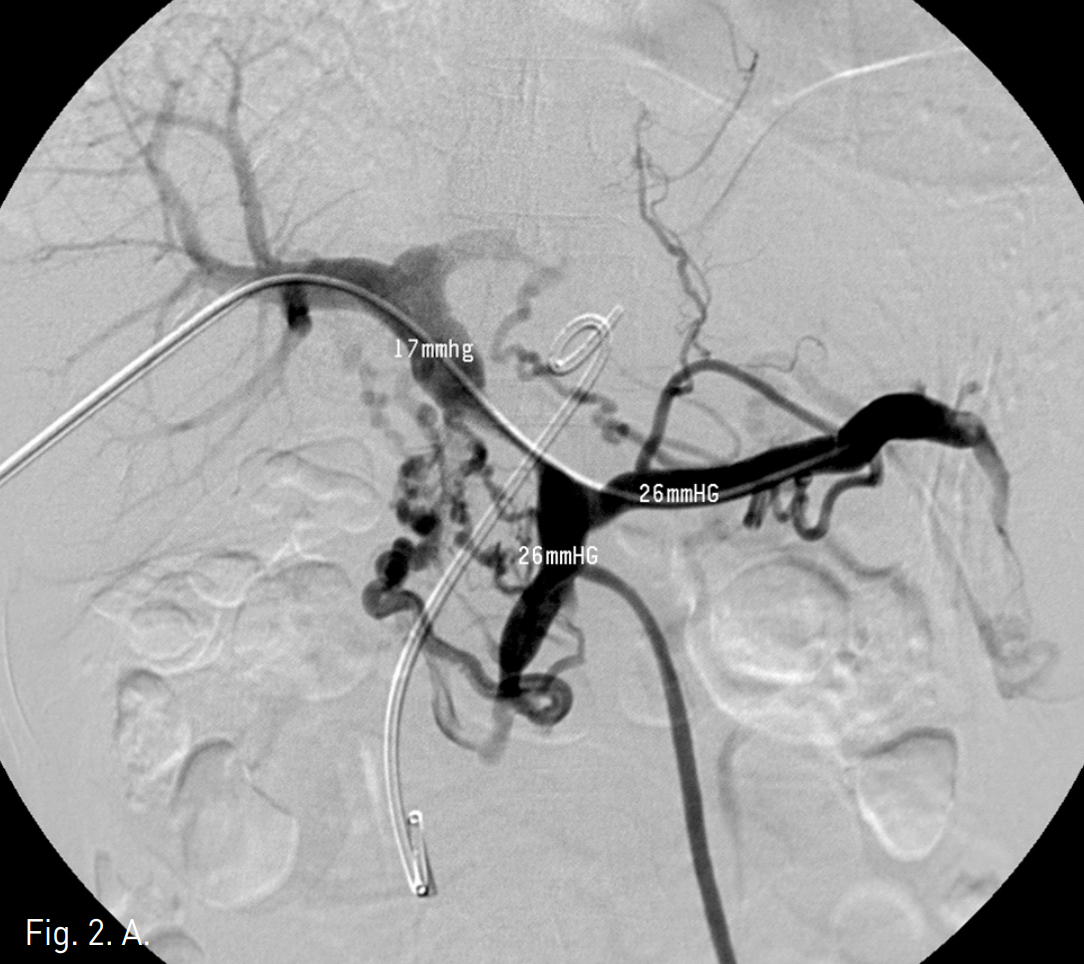

주문맥의 협착부위에서 10mm x 4cm balloon catheter (Synergy, Boston Scientific, Natick, Mass)를 사용하여 풍선확장술을 시행하였으나 elastic recoil로 인하여 반응이 없었음(Fig 2B-C). 자가팽창스텐트(14mm, 6cm, Zilver, Cook, USA)를 협착부위에 설치하고 10mm x 4cm balloon(Synergy, Boston Scientific, Natick, Mass)을 이용하여 post-stent balloon dilatation을 시행함. (Fig 2D)Stent 설치 후 협착 근위부와 원위부의 압력차는 1mmHg (SMV는 18mmHg, 주간문맥은 17mmHg)로 감소되었음(Fig 2E).

Fig. 2

D. Stentis placed in portal vein and post balloon dilatation is performed.